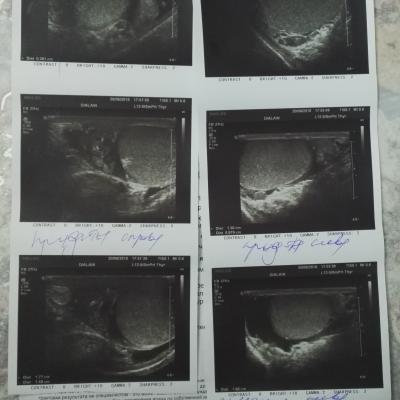

Здравствуйте. 3мая сделали операцию на водянку яичка слева, в ноцк операции почувствовал резкие боли справа. Врачи не понимают в чем дело а я бегаю и показываю УЗИ . Изменился стул, какие то непонятные покалывания по телу, температуры нет.

Нужен осмотр - заочно сложно определить причину болей. По УЗИ - киста придатка яичка, но она не вызывает острые боли. Изменение стула и покалывания по телу - не относятся к урологическим проблемам и не связаны ни с водянкой, ни с кистой. С уважением.